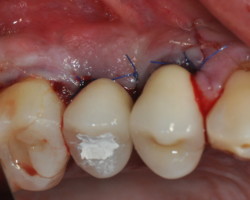

Phase correctrice : redonner les conditions nécessaires au bon maintien de l’hygiène bucco-dentaire (prothétique et/ou chirurgicale).

- Phase correctrice : créer des conditions compatibles avec la maintenance. (chirurgie résectrice, implantoplastie, correction prothétique)

Avant-Après :